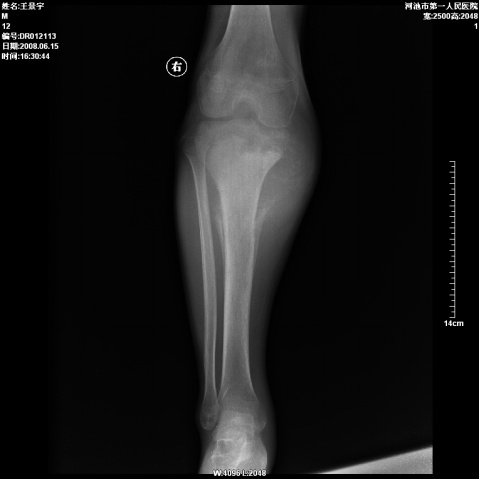

以下是引用随光逐影在2008-6-23 15:30:00的发言:[br]胫骨中上段骨肉瘤(临床表现:好发年龄+好发部位。ct表现:骨质破坏+肿瘤新生骨+骨膜反应并破坏,形成codman氏三角+软组织肿块)。